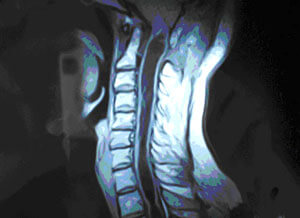

Siringomiýeliýa (grek dilinde sirinx - gamyş, boş tüýdük; miýelon - oňurga ýiligi) – dowamly kesel bolup, oňurga ýiliginde we süýri beýnide boşluklaryň emele gelmegi bilen häsiýetlendirilýär. Bu üýtgemeleriň netijesinde bedeniň uly meýdanlarynda  agyryny we temperaturany aňşyrmak duýgurlylygy ýitýändir.

Emele gelýän boşluklar adatça oňurga ýiliginiň boýun bölüminiň aşaky böleginde, döş bölüminiň ýokarky böleginde ýa-da boýun bölüminiň ýokarky böleginde emele gelip, süýri beýnä (siringobulbiýa) ýaýrap biler. Seýrek ýagdaýlarda bil bölümi ýa-da tutuş oňurga ýiligi zeperlenip bilýändir.